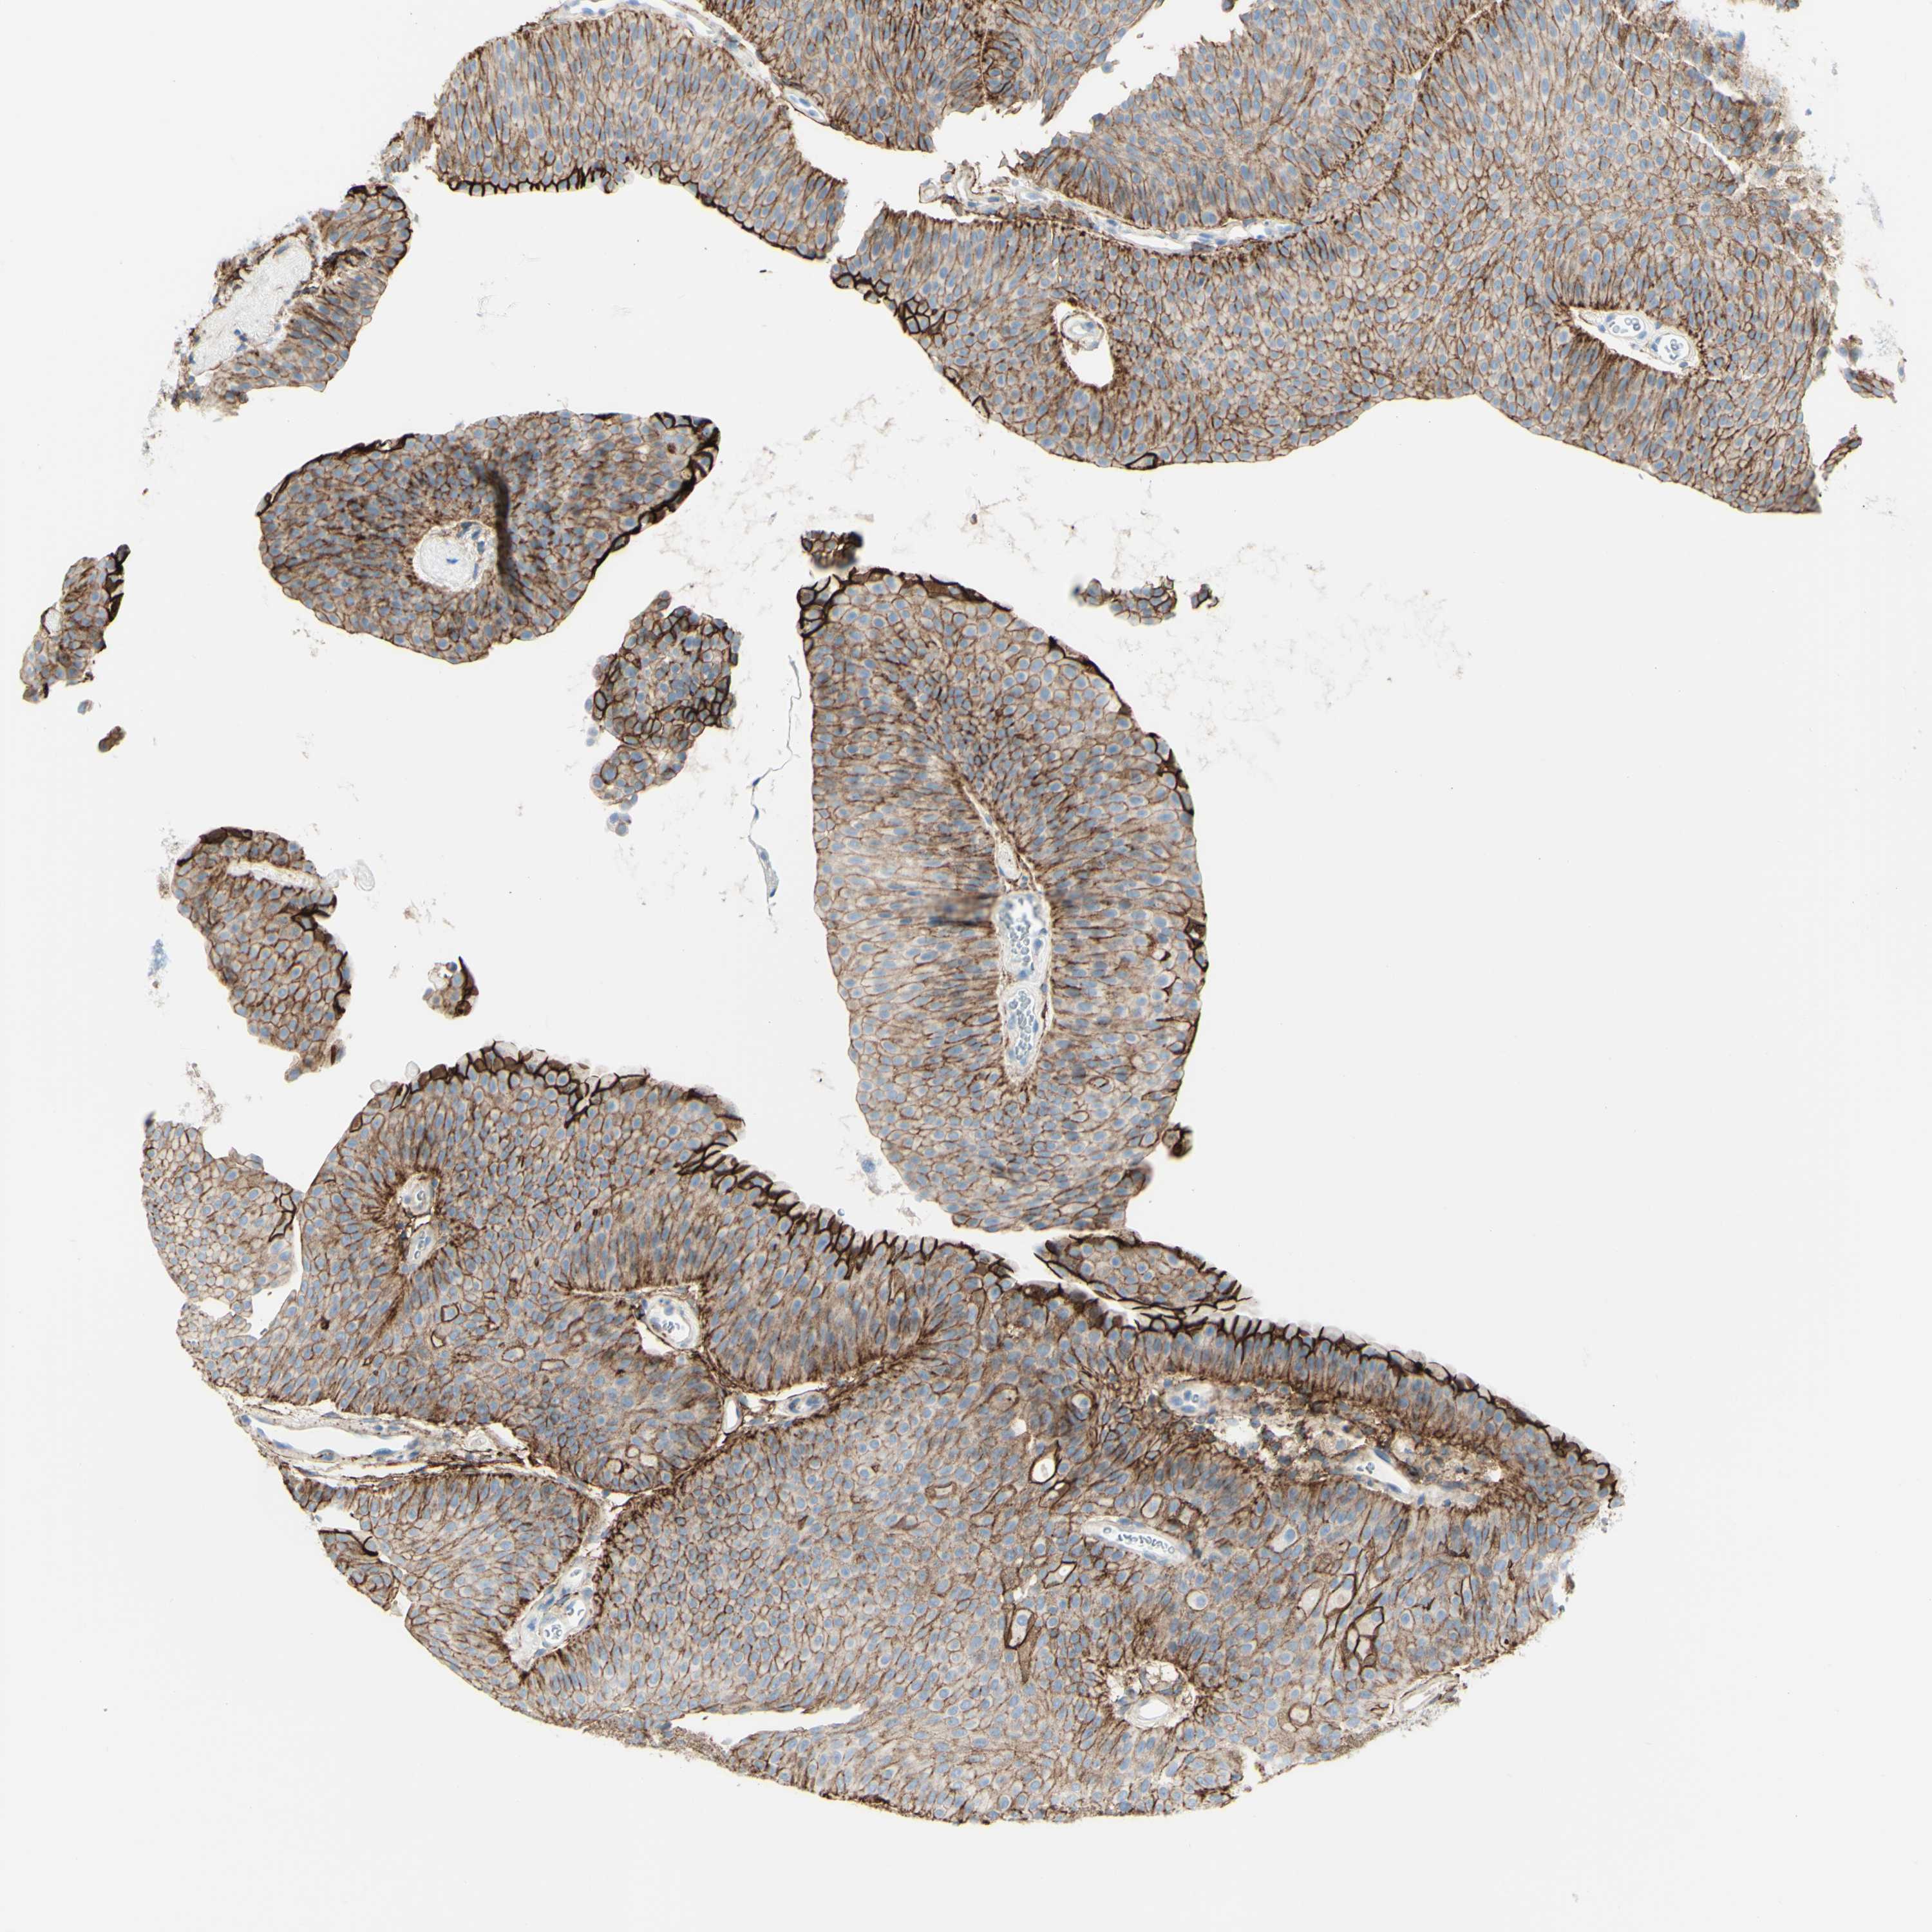

UROTHELIAL CANCER - Protein expressioni

A mouse-over function shows sample information and annotation data. Click on an image to view it in a full screen mode. Samples can be filtered based on level of antibody staining by selecting one or several of the following categories: high, medium, low and not detected. The assay and annotation is described here.

Note that samples used for immunohistochemistry by the Human Protein Atlas do not correspond to samples in the TCGA dataset.

Antibody stainingi

Antibody staining in the annotated cell types in the current human tissue is reported as not detected, low, medium, or high, based on conventional immunohistochemistry profiling in selected tissues. This score is based on the combination of the staining intensity and fraction of stained cells.

Each image is clickable and will lead to virtual microscopy that enables deeper exploration of all samples and also displays staining intensity scores, fraction scores and subcellular localization as well as patient and tissue information for each sample.

Antibody HPA010926

Antibody CAB002148

Urothelial carcinoma, Low grade

Urothelial carcinoma, High grade

Adenocarcinoma, NOS